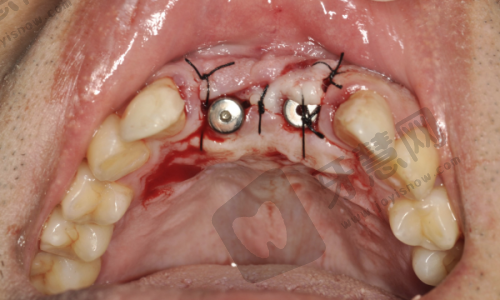

在泉州安格尔口腔开展美国百康种植牙7800元起项目的医生们,具备丰富临床经验和专精知识。他们经过系统口腔医学培训,对种植牙技术有深入研究和掌握。面对患者,医生会详细检查和评估口腔、身体状况及需求,制定个性化种植方案。例如对于骨量不足的患者,采用骨增量技术创造良好条件。种植过程中操作精细,严格遵循手术规范,确保种植体正确植入,密切关注患者反应并及时处理问题。术后还会为患者提供详细护理指导,如告知饮食注意事项,避免食用实力强、过烫食物,保持口腔清洁等。凭借专精技术和负责态度,医生们让泉州安格尔口腔的美国百康种植牙项目得到众多患者认可,帮助患者解决牙齿缺失问题,重新拥有健康美丽的牙齿。